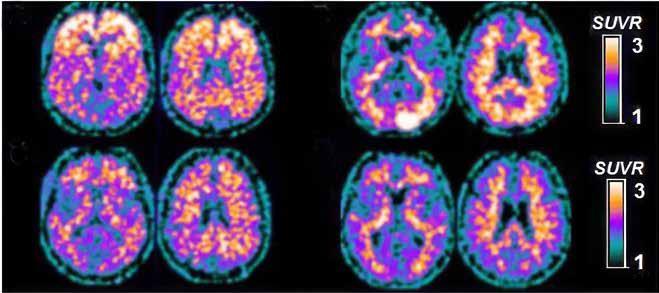

Sammenhængen mellem parodontitis og Alzheimers sygdom / 566

Vi ser på sammenhængen mellem parodontitis og Alzheimers sygdom, og om intensiv parodontologisk behandling kan medvirke til at forebygge og bremse demensudvikling.